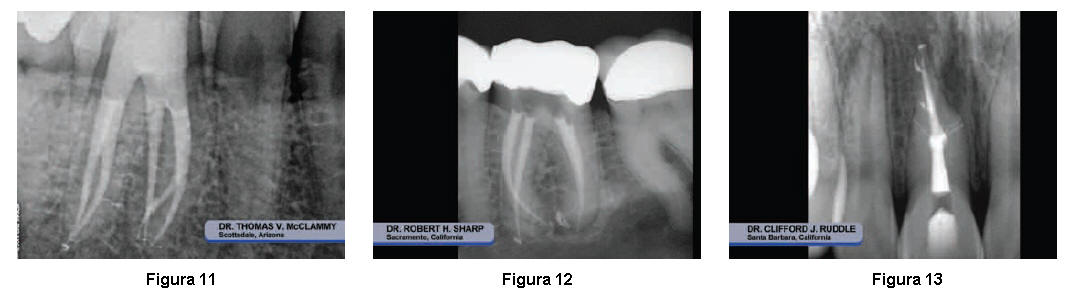

Sistemas de conductos limpios y permeables,  proporcionan el éxito de la obturación 3D  a largo plazo (Figuras 11- 14).

Figura 14